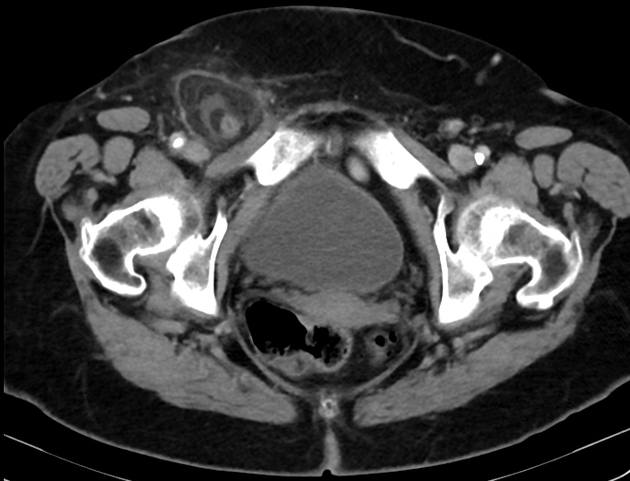

Thoát vị De Garengeot

» Thông tin: Nữ giới – 85 tuổi.

» Lâm sàng: Đau háng phải.